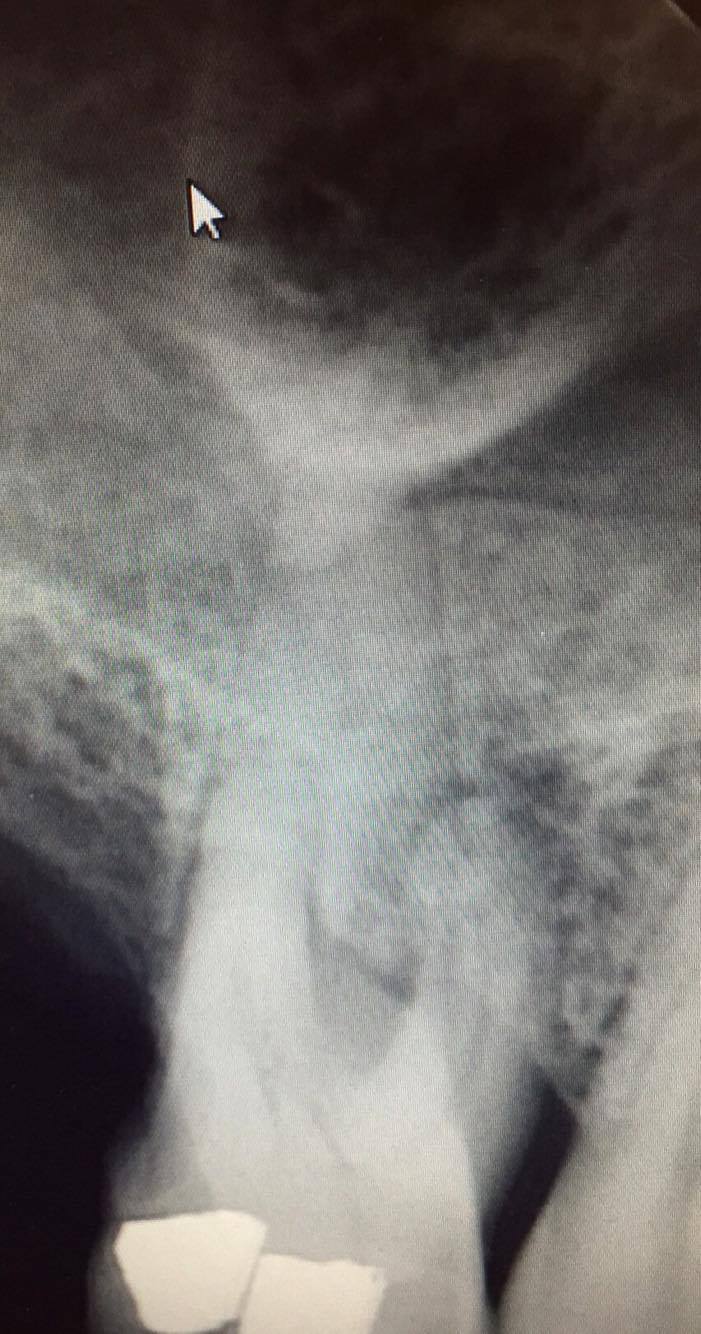

Bonjour, pensez voous qu'il est utile de couronner cette 16 apres la devitalisation par rapport a la perte osseuse?

Mobilité? Sondage paro? Traitement paro global envisagé?

Avec si peu d'élément répondre c'est du pifomètre.

Donc au pifomètre tu fais l'endo tu fais une reconstitution provisoire et si la lésion cicatrise tu peux couronner.

Déjà poser l'indication de l'endo, si la dent n'est pas conservable pour raison paro tu peux directement passer à l'exo.